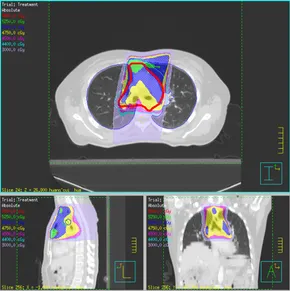

图片

一名53岁女性患者于2008年6月确诊鼻咽癌,随即接受放化疗,治疗3个月后病情得以缓解。

2009年7月发现其癌细胞向右上肺纵膈淋巴转移,后对其进行了右上肺切除术及纵膈淋巴结清扫术。术后,她完成了5个周期的吉西他滨和顺铂(GP)方案化疗及25次放疗。放疗结束后3周,她开始接受DC-CIK治疗,共计5次。

在之后对该患者连续随访13年,未见其肿瘤复发、转移及发生严重不良反应。

该案例展示了术后放化疗联合DC-CIK免疫治疗对鼻咽癌伴肺及纵隔淋巴结转移患者取得了较好的治疗效果,这表明放化疗联合免疫治疗可能是一种安全有效的治疗方案。